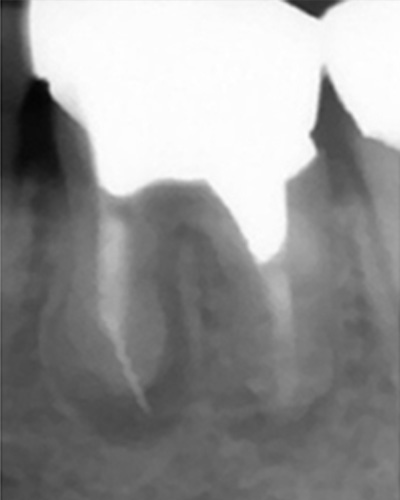

こちらのレントゲン写真を見てください。どちらかの歯医者さんで神経を取っています。根管に入れる薬は白く映ります。赤矢印部分です。一番右側が模式図ですが、青い部分が薬、根っこの先の赤点が化膿している部分です。

薬がほとんど入っていないのがわかります。黄矢印部分です。青矢印まで薬が入らないといけないのですが、全く入っていません。その結果、根っこの先が黒くなっています。膿が貯まって化膿すると黒く写ってくるのです。

別な歯科医院で治してもらいました。薬が根の先まで入っているのがわかります(黄矢印)。 根尖の黒い影が消失しています(赤矢印)。骨が再生すると白く写るようになります。

ガッタパーチャポイントは、理想的には歯根(シコン)の先ピッタリが良いと言われています。

上の図にあるように神経の管に入れる薬が根尖(コンセン)まで入っていなかったり、途中までしか入っていなかったり、薬がスカスカだったりするとその空間にばい菌が繁殖して感染を起こします。

①の写真はどちらかの歯医者さんで神経を取ってもらったレントゲン写真です。根っこの中に薬が全く入っていません。

根の先を見ると小豆ぐらいの大きさの黒い影が見えます。根の中でばい菌が繫殖し感染を起こすとこのような黒い影ができます。黒い影の部分は膿(ウミ)が貯まっています。こうなると腫れて痛みが出てくるのです。

③、④の写真はそれを治した後のレントゲン写真とその模式図です。白く映っている薬が根の先まできちんと入っているのが確認できます。そして根の先にあった黒い影が消えているのが分かります。根の先の炎症が治って、骨が再生すると白く映るのです。

薬が真ん中までしか入っていないため、膿が貯まっている。

奥の歯も薬が入っていない。

薬が根尖までしっかりはいっていない。

化膿している

小豆大の病巣

ワッテが入っていた 病巣も大きい

突き出たガッタパーチャポイントと大きな病巣

なぜか根管途中から突き出たガッタパーチャポイント